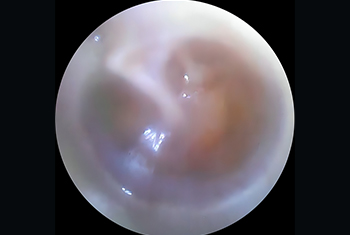

Comprehensive care for ear infections and hearing loss, including Tympanoplasty, Mastoidectomy, Ossiculoplasty and Stapedotomy/Stapedectomy for improved hearing outcomes.